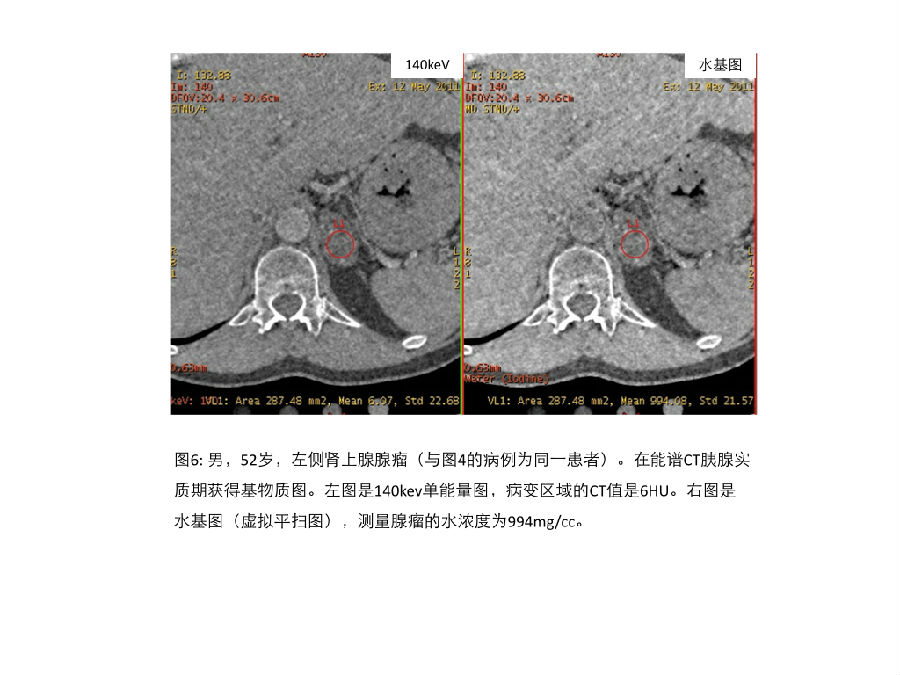

研究小组应用传统平扫图像和能谱特征性的水基图、脂肪基图和140keV图 对一组肾上腺富脂肪病变和乏脂肪病变进行了分析,证实了能谱的这些特征性参数和传统CT值之间具备很好的相关性。能谱CT可以提供确诊富脂质腺瘤的的诊断阈值,这个阈值具备很高的特异性。 Using rsDECT, our group evaluated arterial phase water(–iodine), fat(–iodine), and pseudo-unenhanced 140 keV images compared to conventional unenhanced scans in the same subjects and found strong correlation between these rsDECT variables and accepted single- energy MDCT attenuation values for high lipid-content and low lipid-content adrenal lesions. Clinically relevant thresholds on rsDECT that identified lipid-rich adenomas with high specificity were determined (Weber et al. (2012) presented to the Society of Abdominal Radiology, unpublished data).